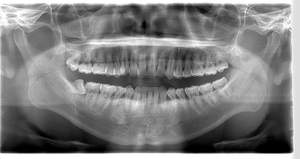

- 抜歯前写真(レントゲン)

- 抜歯前写真(CT画像)

| 年齢 | 20代・女性 |

|---|---|

| 主訴 | 左下親知らずがたまに痛み、できれば痛くなく抜きたい |

| 親知らずの生え方 | 完全に埋まっている、横向きに生えている |

| 抜歯時間 | 50分 |

| 費用 | 約8,000円(保険診療、CT代含む) |

| 抜歯内容 | 左下親知らずが横向きになって半分埋まっている状態だったため、麻酔を行い、親知らずの奥の歯ぐきに切開をいれ、歯が囲んでいる骨を削り、歯の頭の部分を削って出し、その後根の部分に器具をかけて抜歯しました。 親知らずが一部神経に近い部分があったため、術後に麻痺が出る可能性がありました。このケースでは事前にCTを撮影し、歯の位置、根の方向、神経との距離を確認していたため、幸い麻痺が出ることはありませんでした。 術後1週間経過して糸取りをして治療は終了となりました。抜歯後3日間は腫れと痛みで大変だったが、糸取りをする頃には痛みも腫れも無くなったと患者さまも喜んでおられました。 |